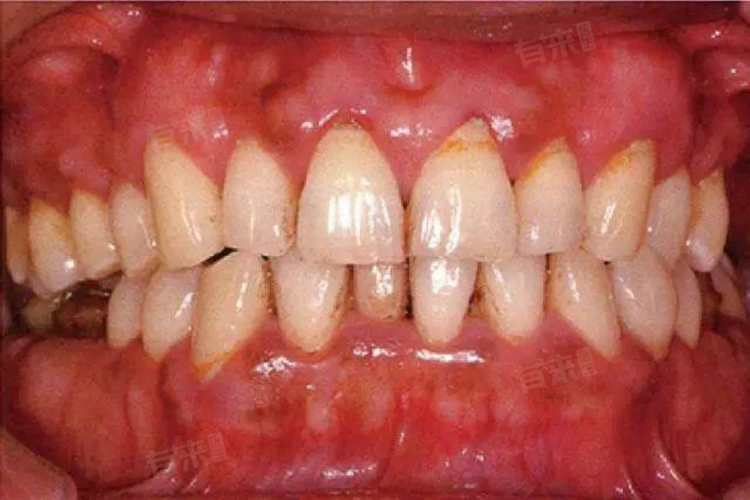

牙龈组织受到炎症的刺激,会出现充血、水肿和疼痛反应,牙龈呈现红肿状态,有时伴有疼痛。